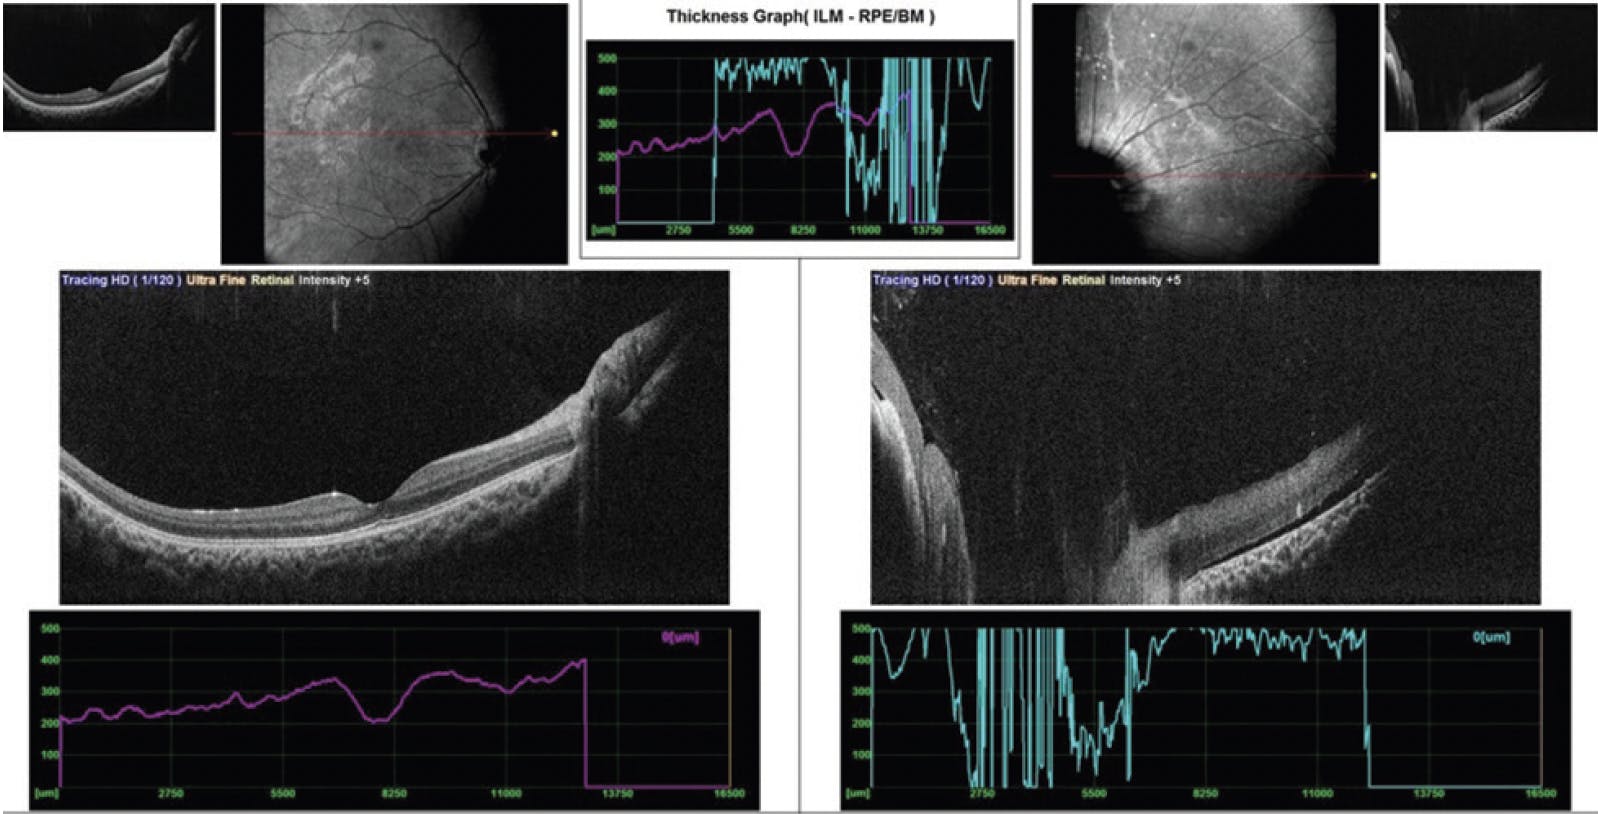

A 1.5-year-old boy, born prematurely at 7.5 month’s gestation, presented with dimness of vision in each eye since birth. The patient had received anti-VEGF injections for stage 4 retinopathy of prematurity elsewhere. Dilated fundus examination of each eye showed fibrovascular proliferation at the disc with large areas of avascularization in the left eye. OCT of each eye showed an altered foveal contour (Figure 7). The patient underwent barrage laser treatment to the avascular zones.

<p>Figure 7. OCT of each eye shows an altered foveal contour.</p>

Figure 7. OCT of each eye shows an altered foveal contour.